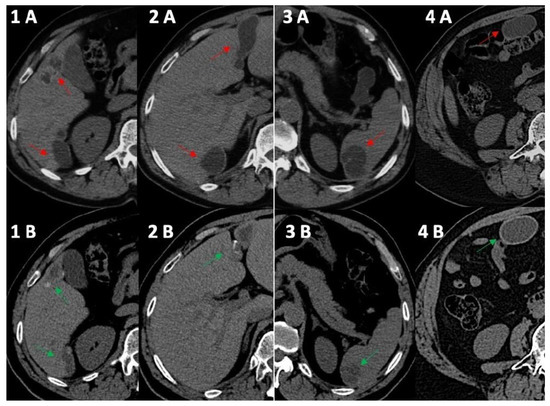

Figure 1.

Computed tomography comparative imaging of some Echinococcus cysts in 2011 (A, red arrow) and in 2021 (B, green arrow). The cysts are located in liver segments 5 ((1A) 15 × 35 mm vs. (1B) 15 × 20 mm) and 6 (1–(2A) 41 × 45 mm vs. (1B) 10 × 36 mm), in segments 3–4 ((2A) 20 × 68 mm vs. 2B 19 × 45 mm), in the upper pole of the spleen ((3A) 30 × 40 mm vs. (3B) 30 × 30 mm), and in the right inframesocolic space ((4A) 41 × 22 mm vs. 4B 40 × 26 mm). In 2021, CT scans (1B,2B,3B) showed some initial signs of cystic wall calcifications that were not present in 2011 (1A, 2A, 3A). Uncertainty persisted for the right inframesocolic cyst (4B), but in 2023 (Figure 2, #3), US demonstrated signs of intracystic degenerative content (Figure 2—n3).

In 2014, the anti-Echinococcus titers were still elevated, serum AST, ALT and GGT were normalized and imaging of the cysts suggested possible activity especially for the peritoneal localizations; therefore, treatment with ABZ was re-started and continued until 2021. Normal hepatic blood test results were observed until the end of treatment with ABZ in 2021 (Table 1) and a final (2021) hepatic FibroScan demonstrated normal stiffness values (May 2021, 2.8 kPa). We observed no significant change in the eosinophil count for the whole duration of the follow-up (Table 1), thus excluding a significant relationship between eosinophilia in this case of cystic echinococcosis [10]. Finally, at the end of 2021, the patient had received a total of 15 complete cycles with ABZ that equaled 1260 days of treatment. All cystic lesions progressively showed US [11] and CT signs of regression (Figure 1 and Figure 2) with some uncertainty for peritoneal lesions, which are still in follow-up in 2023. In particular, based on WHO-IWGE US classification [11], in 2023, all cysts were defined as inactive (CE4–5; Figure 2, frame 1, 2, 4, 5) with the exception of the peritoneal lesion that was considered transitional (CE3; Figure 2, frame 3).